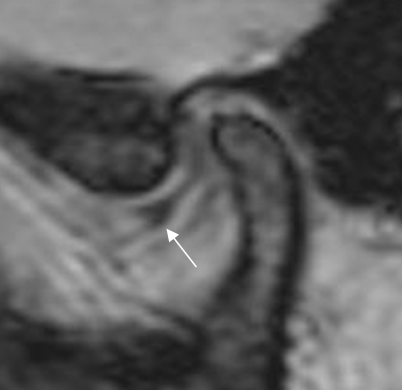

El hallazgo mas frecuente es el desplazamiento anterior del disco. (2). La banda posterior se localiza por delante del cóndilo y al abrirla boca, se produce un chasquido, que corresponde a la reacomodación o reducción. Con la progresión de la alteración, no se produce la reducción. (Fig 7, 8 y 9).

Fig 7. Disco luxado.

RM GE sagital oblicuo con boca cerrada. Desplazamiento anterior del disco. Banda anterior. (Flecha delgada).